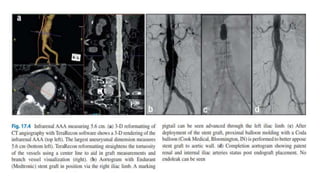

Endovascular AAA repair (EVAR)

• This is a less invasive and modular aortic repair system and involves

delivering stent grafts from the access vessels, usually from the

common femoral artery.

• Deployment of the stent creates a conduit within the aorta using a

stent covered in low-porosity graft material which is sealed by

outward force at the proximal and distal contact points in order to

completely exclude blood flow to the aneurysmal sac.

Abdominal and ThoracicAortic Aneurysms • Abdominal Aortic Aneurysm (AAA) • Abdominal aortic aneurysms can be categorized into four subtypes based on the proximal extent: suprarenal, pararenal, juxtarenal, and infrarenal. • Society for Vascular Surgery guidelines for AAA repair: Diameter ≥5.5 cm in men, ≥5.0 in women Rapid enlargement, >0.5 cm/6 month period or >1 cm/year Symptomatic Rupture

Endovascular AAA repair(EVAR) • This is a less invasive and modular aortic repair system and involves delivering stent grafts from the access vessels, usually from the common femoral artery. • Deployment of the stent creates a conduit within the aorta using a stent covered in low-porosity graft material which is sealed by outward force at the proximal and distal contact points in order to completely exclude blood flow to the aneurysmal sac.